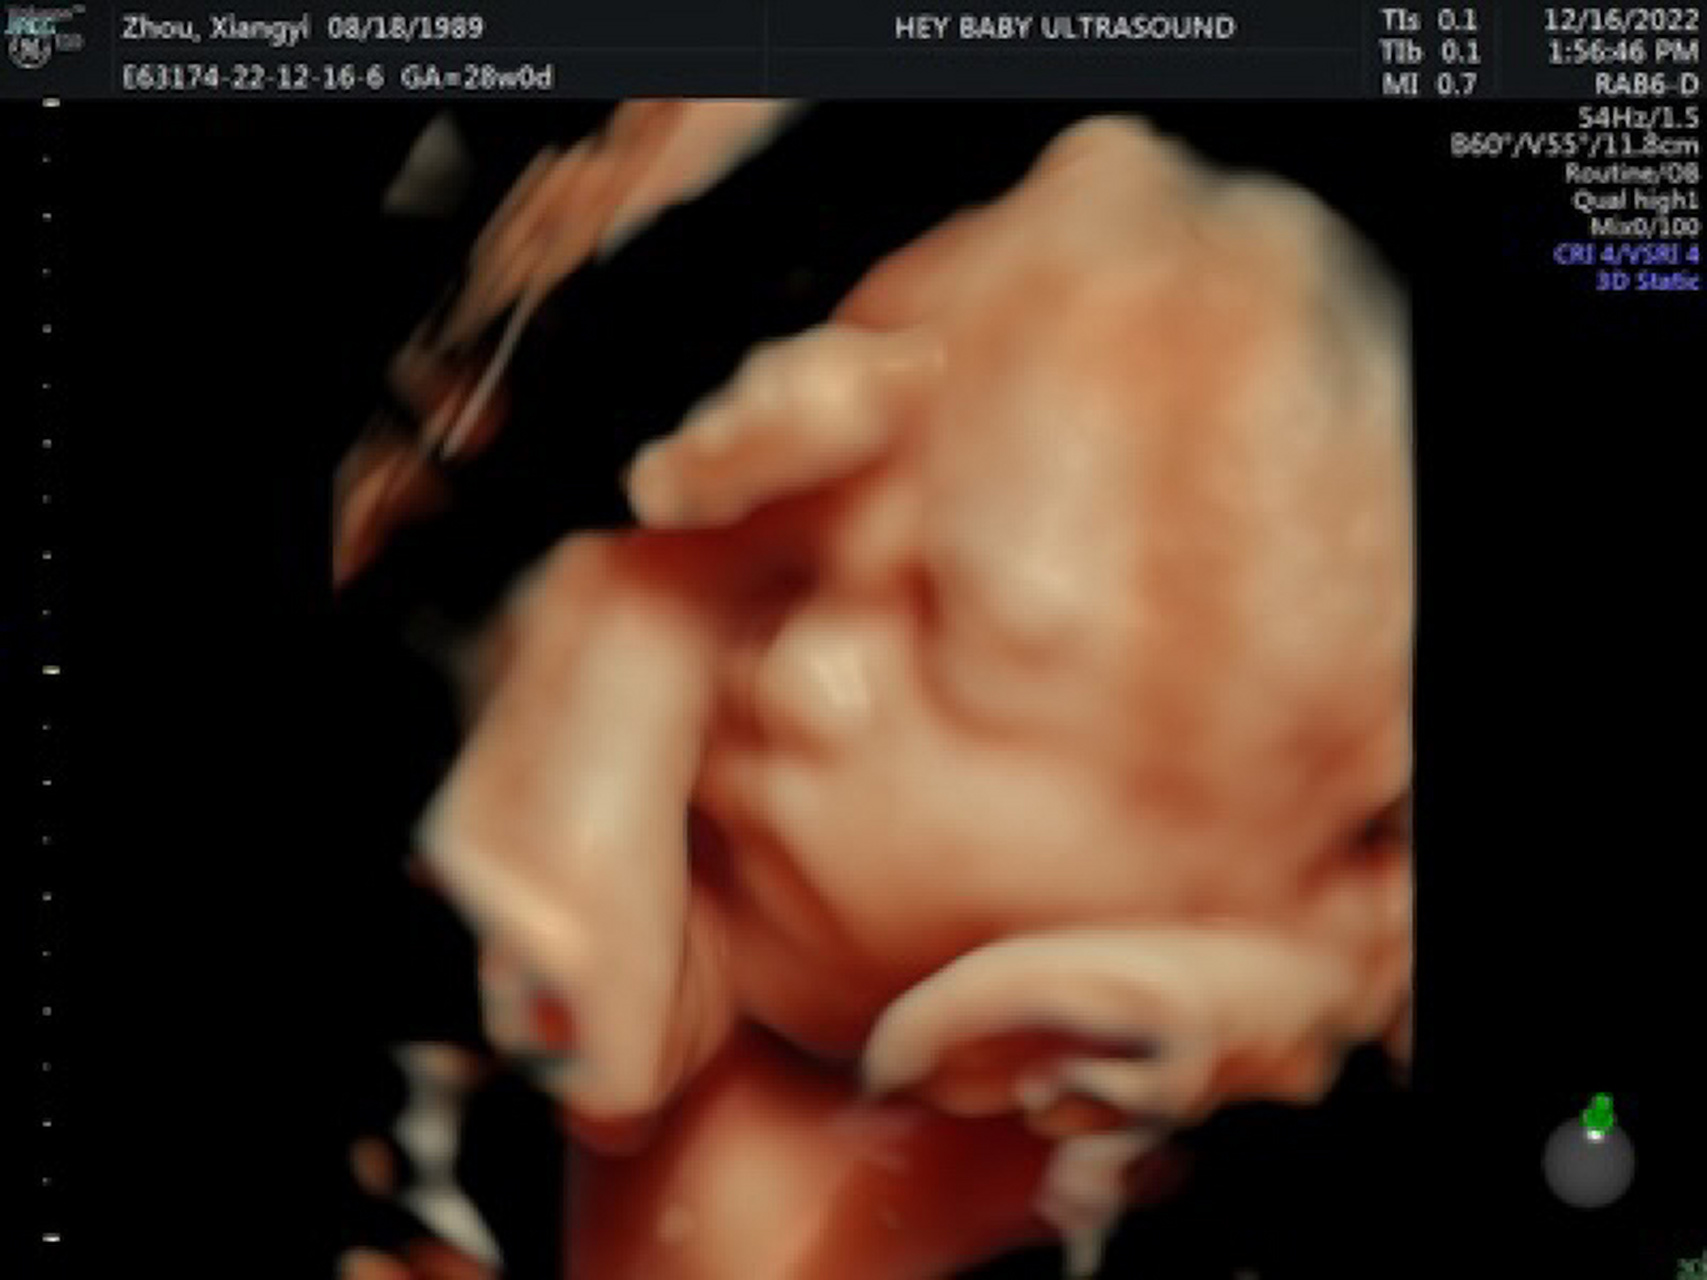

28周了,今天照了四维彩超,宝宝鼻子好大啊 其实我的大排畸一个多月之